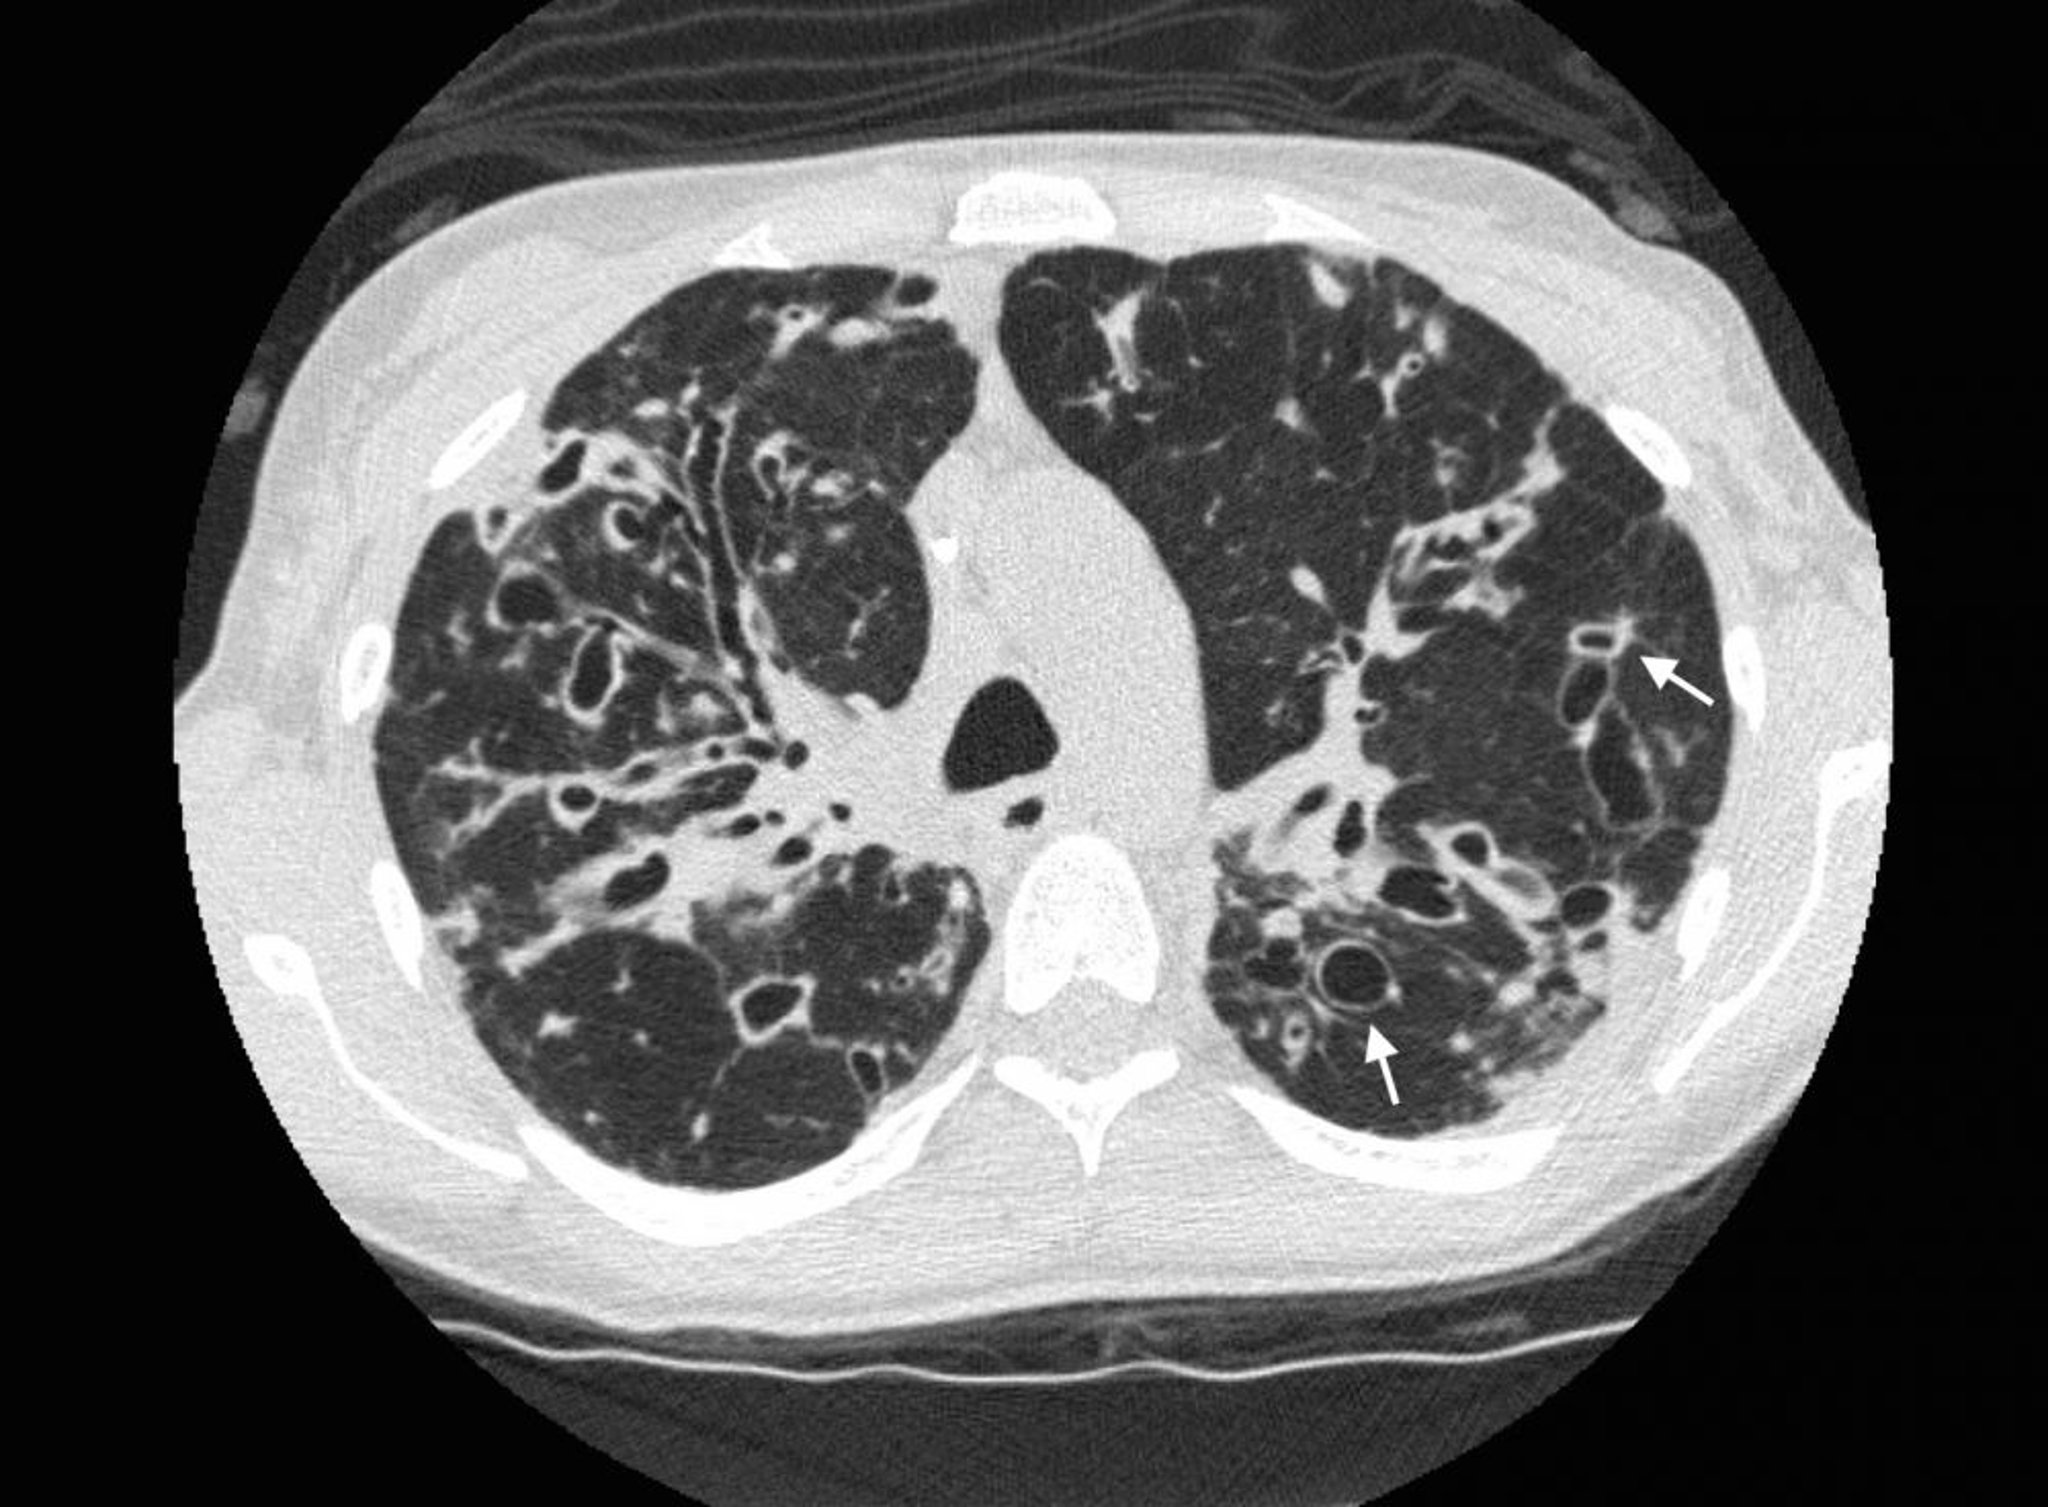

Бронхоектаз (комп'ютерна томографія)

A chest CT in a patient with cystic fibrosis shows severe bronchiectasis in the upper lung zones with dilated airways and cystic changes. Arrows show the signet ring sign, where a dilated airway (the ring) is adjacent to a smaller artery (the top of the ring). Normally, airways are the same size as, or smaller than, the adjacent arteries.

Photo courtesy of Başak Çoruh, MD.